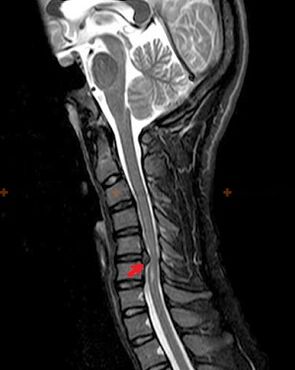

Diagnostikoak eta X izpien seinaleak

Osteokondrosia X izpien diagnostikoa da, argazki kliniko zehatza larriagotzen den unean soilik eskuragarri baitago, eta bizkarrezurra aldaketak pertsona baten ongizate subjektibo osoarekin gerta daitezkeen bitartean. X izpien azterketarik gabe, osteokondrosi susmagarriez bakarrik hitz egin dezakegu, antzeko sintomak beste gaixotasun batzuek (miositisak, ornoetako neoplasiak eta beste) eragin ditzaketelako.

Osteokondrosia diagnostikatzeko, ikerketa-metodo hauek erabiltzen dira: erradiografia (ahal bada proba funtzionalekin), MSCT eta MRI. Azken azterketa hori hobetsi da orno arteko egituren egoera oso argi ikusteko aukera ematen duelako.

Osteokondrosiaren X izpien seinaleak bizkarrezurreko aldaketa hauek dira:

- Orno arteko diskoen altuera murriztua.

- Hezur bazterreko hazkuntzak egotea.

- Ornoen kokapena urratzea elkarren artean.

- Orno-gorputzen eta arkuen deformazioak, etab.

Goian deskribatutako aldaketen presentzia, baita orno arteko diskoaren egituraren aldaketak ere, MSCT eta MRI bidez detektatuta, osteokondrosiaren presentzia baieztatzen duten seinale fidagarri gisa balio dute.